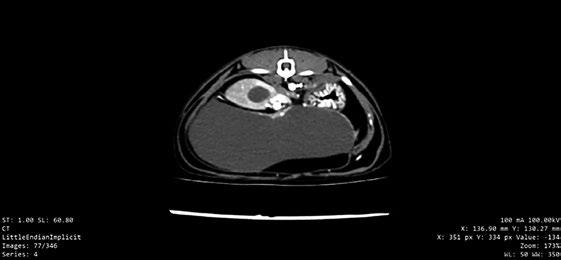

Dada la gravedad del cuadro y el estrés del animal, se decidió sedarlo con una dosis única de midazolam (0,2 mg/kg) y butorfanol (0,2 mg/kg) y se introdujo en una cámara de oxígeno. Durante su estancia en la cámara, se monitorizó la saturación de oxígeno (siempre por encima del 92 %) y la presión sanguínea sistólica (108 mmHg, rango 100-140 mmHg).

T-POCUS

Se optó por una T-POCUS al no considerar al animal lo suficientemente estable para realizar radiografías y ecocardiografía completa. En decúbito esternal para evitar el estrés. Se observaron gran cantidad de líneas B compatibles con presencia de

líquido intersticial pulmonar (más de tres por campo pulmonar), lo cual es compatible con edema pulmonar cardiogénico o no cardiogénico, procesos inflamatorios o infiltrativos (traumatismos, SRIS, bronquiolitis) o fibrosis intersticial. Se confirmó hipertrofia del VI y dilatación de AI. El aumento del AI junto con la presencia de líneas B puede sugerir con mayor probabilidad un edema pulmonar de origen cardiogénico (Ward et al. 2017).

Estudio radiológico

En las vistas laterales, el vertebral heart score (VHS) era de 7,75 vértebras (rango 6,7-8,1). No se observó desplazamiento dorsal de la tráquea, ni mayor apoyo cardiaco sobre las estérnebras teniendo en cuenta la edad del paciente. Se observó un patrón alveolar en zonas caudodorsales al corazón (figura 1), y patrón intersticial difuso generalizado. En la vista dorsoventral, se apreciaba una silueta cardiaca con forma de “corazón de San Valentín”, sugestivo de aumento del AI o bilateral de atrios (figura 2).

La prueba de elección para diagnosticar ICC es la radiografía torácica. En nuestro caso retrasamos su realización y realizamos una T-POCUS dada la inestabilidad del paciente. La T-POCUS cada vez tiene mayor uso en casos de ICC para su diagnóstico, mediante la visualización de líneas B en los diferentes campos pulmonares (Ward et al. 2017), tal y como ocurrió en nuestro caso.

Mediante la radiografía torácica, se determina un VHS normal en gatos de 7,5+/- 0,3 (Buchanan 2000). Esta técnica tiene una sensibilidad baja y especificidad elevada (28 % y 95 %, respectivamente) (Soyeon et al. 2023) para la detección de agrandamiento de AI. Esto se refleja en nuestro paciente, con un VHS de 7,75 (normal), pero un aumento considerable de AI ecocardiográficamente.